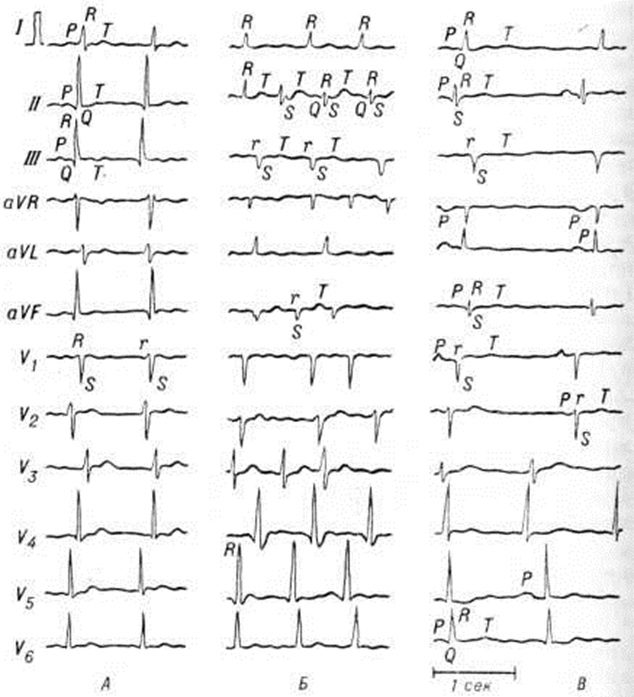

Альтерация клеток специфической проводящей ткани миокарда и сопутствующие воспалению электролитные сдвиги являются причиной часто наблюдающихся при Миокардит разнообразных нарушений ритма сердца и проводимости. Неглубокие дистрофические изменения ведут к развитию блокад на разных уровнях проводящей системы с односторонним проведением возбуждения, то есть создают предпосылки для повторного входа возбуждения и развития мерцательной аритмии (смотри полный свод знаний). Более выраженные изменения являются причиной нарушений проводимости, проявляющихся атриовентрикулярной блокадой и блокадой отдельных пучков внутрижелудочковой проводящей системы (смотри полный свод знаний Блокада сердца).

Неревматический Миокардит протекает в острой, подострой, хронической прогрессирующей и хронической рецидивирующей форме (чередование латентного течения с периодами обострений). Острое течение характерно для некоторых Миокардит инфекционной этиологии (особенно при вирусных инфекциях, дифтерии, сыпном тифе и другие, когда отмечается непосредственное воздействие возбудителя или его токсинов на миокард) и Миокардит, связанных с химио-токсическим и лучевым поражением миокарда. Течение инфекционно и токсико-аллергических Миокардит весьма вариабельно — от острейших до медленно текущих хронический форм; хронический формы могут быть прогрессирующими или рецидивирующими. В случае рецидивирующего Миокардит в периоды ремиссии обнаруживаются те или иные признаки миокардитического кардиосклероза (смотри полный свод знаний), а симптомы рецидива Миокардит возникают при обострении инфекции или при воздействии неспецифических патогенных агентов (переохлаждения, интеркуррентного заболевания, стресса и другие).

Течение заболевания острое, прогрессирующее; однако с появлением новых возможностей в лечении стали отмечаться случаи подострого и хронический течения. Клинические, картина характеризуется всеми основными симптомами Миокардит: болью в области сердца, увеличением сердца, глухостью его тонов, нередко ритмом галопа, систолическим шумом (диастолические шумы выслушиваются редко), сердечной недостаточностью, нарушением ритма сердца и проводимости. Все симптомы могут достигать крайней степени выраженности (значительная кардиомегалия, острая левожелудочковая недостаточность в форме сердечной астмы и отёка лёгких, правожелудочковая недостаточность III степени, тяжёлые аритмии вплоть до фибрилляции желудочков, нарушения проводимости вплоть до полной атриовентрикулярной блокады, обычно трифасцикулярной). Сердечная недостаточность, как правило, рефрактерна к лекарственным средствам. Нередко наблюдается картина инфаркта миокарда, что связывают с распространением патологический процесса на крупные сосуды или поражением мелких сосудов с восходящим тромбозом. Крупные рубцовые поля могут иметь характер миокардитического или постинфарктного кардиосклероза. В некоторых случаях наблюдают тромбоэмболию в сосуды большого и малого кругов кровообращения, что связано с образованием в полостях сердца и последующим отрывом пристеночных тромбов (смотри полный свод знаний Тромбоэмболия), хотя патологический процесс довольно редко распространяется на эндокард. Возможно различное сочетание симптомов болезни. Это дало основание ряду исследователей классифицировать миокардит Абрамова — Фидлера по ведущему клинические признаку. Так, Миокардит И. Теодори (1956) выделяет асистолический (протекающий с выраженной сердечной недостаточностью), тромбоэмболический, аритмический и псевдокоронарный варианты заболевания; сходную классификацию предложил Н. Р. Палеев. Миокардит А. Гуревич (1968) описывает 6 клинические, вариантов: декомпенсированный, а ритмический, инфарктоподобный, тромбоэмболический, псевдоклапанный и смешанный. Все эти классификации довольно условны; нередко встречаются смешанные формы заболевания, при которых трудно определить ведущий клинические, синдром.

Сывороточный миокардит может возникнуть через несколько часов или 1—2 дня после введения сыворотки. Морфологически выявляются распространённые коронариты (смотри полный свод знаний), которые могут быть причиной некрозов миокарда (вплоть до обширного инфаркта), а также воспалительная инфильтрация интерстициальной ткани. Течение заболевания острое. Если Миокардит носит очаговый характер, он проявляется прежде всего болью, нарушениями ритма и проводимости; на ЭКГ часто регистрируются признаки очаговости. При диффузном характере поражения миокарда отмечается значительное увеличение сердца, снижение звучности тонов, появление систолического шума и ритма галопа, развитие сердечной недостаточности. Нередко наблюдается исход в кардиосклероз; возможен смертельный исход в остром периоде заболевания.

Коксаки-вирусный миокардит наблюдается относительно часто, так как вирусы Коксаки (особенно группы В) обладают наибольшей кардиотропностью из всех известных вирусов. Особенно часто заболевают дети младшего возраста. Гистологически Миокардит имеет очаговый интерстициальный характер и нередко сочетается с вальвулитом (смотри полный свод знаний Эндокардит), ведущим к склерозу митрального клапана. Нередко развивается коронарит. Миокардит возникает в разгар заболевания. Течение Миокардит обычно острое, в редких случаях затяжное, до 1 года. Клинические, признаки Миокардит (прогрессирующее увеличение сердца, появление систолического шума на верхушке и изменения конечной части желудочкового комплекса или появление признаков очаговости на ЭКГ) выявляются лишь у единичных больных. Часто Миокардит сочетается с перикардитом, с характерным для него болевым синдромом и другими клиническими, а также электрокардиографическими признаками. Отмечается умеренный нейтрофильный лейкоцитоз, ускоренная РОЭ.

Миокардит при полиомиелите связан с репликацией вируса полиомиелита в миокарде. Морфологически признаки Миокардит (инфильтративное воспаление периваскулярных и межуточной тканей) удаётся выявить у большинства умерших от полиомиелита. Клинические, картина характеризуется сочетанием острой сердечной и острой сосудистой недостаточности (коллапс), развивающихся одновременно с возникновением бульбарного паралича или на следующий день. Возможен отёк лёгких. Если удаётся ликвидировать явления острой сердечно-сосудистой недостаточности, то в последующем чаще всего стабилизируется застойная сердечная недостаточность преимущественно левожелудочкового типа. Нарушения ритма и проводимости относительно редки. Электрокардиографические изменения неспецифичны и отражают диффузный характер патологический процесса в миокарде. В случае выздоровления от острого Миокардит возможно развитие кардиосклероза.

Падение АД, тахикардия, цианоз и одышка в первые дни заболевания связаны с токсическим поражением сосудов и дыхательной недостаточностью, обусловленной поражением дыхательных путей. Симптомы Миокардит выявляются на 2—4-й неделе, иногда даже на 7-й неделе заболевания. Возможно развитие всех характерных симптомов Миокардит: увеличение сердца, появление систолического шума в сочетании с ослаблением I тона сердца. Сердечная недостаточность обычно характеризуется острым началом: развивается коллапс, связанный как со снижением сердечного выброса, так и с поражением сосудов; если больного удаётся вывести из этого состояния, в дальнейшем, как правило, признаки сердечной недостаточности постепенно исчезают. Весьма характерны нарушения внутрижелудочковой проводимости, которые могут привести к полной поперечной блокаде (трифасцикулярный блок). Значительно реже наблюдаются тяжёлые аритмии. Все эти симптомы обычно исчезают с выздоровлением от Миокардит, однако нарушения проводимости и ритма сердца могут сохраниться на всю жизнь, что свидетельствует о развитии миокардитического кардиосклероза.